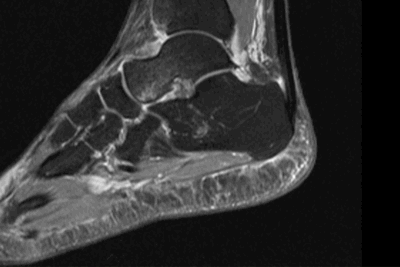

МРТ голеностопного сустава

Минимальные костные повреждения, обычно не выявляемые при рентгене, хорошо визуализируются при МРТ и КТ.

Для выявления изменений внесуставных стабилизаторов голеностопного сустава УЗИ и МРТ имеют примерно одинаковую диагностическую информативность. Оптимальным видом лучевого исследования для выявления изменений внутрисуставных структур голеностопного сустава является МРТ.

МРТ является наиболее универсальным методом визуализации повреждений всех структур голеностопного сустава. КТ позволяет детализировать (оценить степень и распространенность) выявленных при МРТ минимальных костных переломов. Повреждение связок по данным некоторых авторов в 16-21% случаев сопровождает спортивные травмы голеностопного сустава. При острой травме чаще всего повреждается передняя таранно-малоберцовая связка, реже - пучки дельтовидной связки.

Поскольку острые повреждения связок редко лечатся хирургически, магнитно-резонансная томография чаще всего назначается при наличии клинических признаков нестабильности сустава для решения вопроса о тактике ведения пациента и профпригодности.

МРТ критерии диагностики острых разрывов включают изменение интенсивности сигнала внутри и вокруг связок, прерывистость волокон, исчезновение жировых включений в структуре связки, признаки отека окружающих мягких тканей, контузию сочленяющихся костей.

По данным P.W. Bearcroft и соавт. чувствительность МРТ в выявлении острых повреждений связок голеностопного сустава составляет 94-96%, для хронических разрывов – 82-90%. МРТ обладает наибольшей чувствительностью (96-97%) и специфичностью (98%) в выявлении стрессовых переломов на ранней стадии.